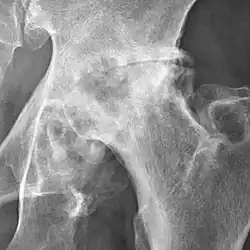

Osteoarthritis of the hip joint may also be graded by Tönnis classification. There is no consensus whether it is more or less reliable than the Kellgren-Lawrence system.[8]

Severe (Tönnis grade 3) osteoarthritis of the hip.

3 Severe:

• large bone cysts

• severe joint space narrowing, or joint space obliteration

• severe deformity of the head